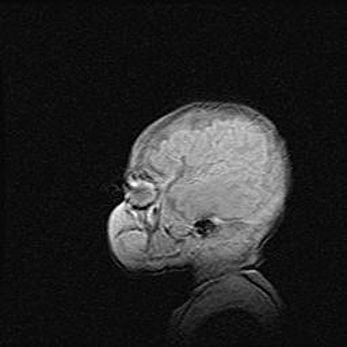

Мальформация Денди-Уокера. Киста задней черепной ямки.

Агенезия мозолистого тела.

Возраст: 2,5 месяца

Вес: 2420 г

Пол: женский

Окружность головы: 37 см

Срок гестации: 32 недели

Мальформация Денди—Уокера — редкий вид патологии ЦНС, представляющий собой врожденный порок развития каудального отдела ствола и червя мозжечка, ведущий к неполному раскрытию срединной (Мажанди) и латеральных (Лушка) апертур IV желудочка мозга. Для этогно синдрома характерна триада симптомов: гипотрофия червя мозжечка и/или полушарий мозжечка, кисты задней черепной ямки, гидроцефалия различной степени. В 70% случаев порок сочетается и с другими аномалиями головного мозга, в частности с агенезией мозолистого тела.